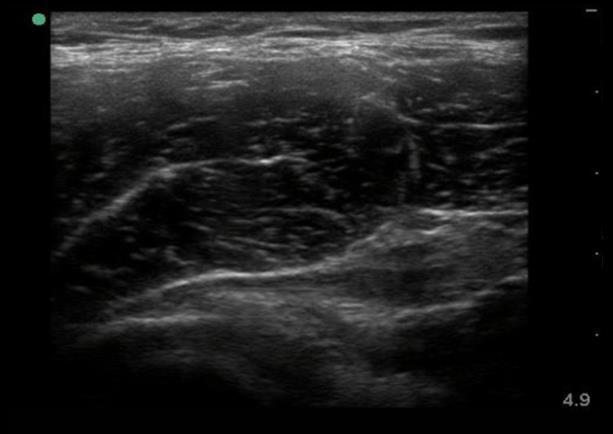

Hip Anterior Lateral Indirect Rectus Long Axis Image